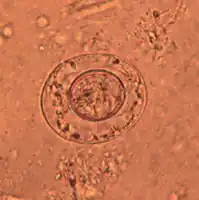

Jaja H. diminuta są okrągłe lub owalne, wielkości 70-86 na 60-80 µm, mają prążkowaną błoną zewnętrzną oraz cienką gładką błoną wewnętrzną. Przestrzeń między tymi błonami jest gładka lub słabo ziarnista. Onkosfera ma sześć haczyków. Jaja H. nana są mniejsze niż H. diminuta, owalne, wielkości 30-55 µm. Na wewnętrznej błonie występują dwa bieguny, z których wychodzą filamenty, biegnące między błonami w liczbie 4 do 8. Onkosfera ma sześć haczyków[2].